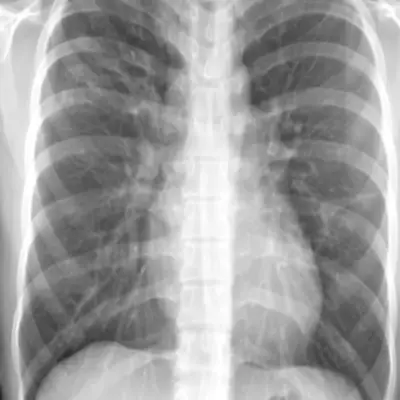

결핵 증상 중 하나로 호흡 곤란을 일으키는 경우가 있습니다. 폐에 결핵균이 침투하면 폐 조직을 손상시키고 염증을 유발하여 호흡 곤란을 초래할 수 있습니다. 환자들은 숨 쉬기가 어려워지고 가벼운 활동이나 일상적인 동작도 어려울 수 있습니다.

호흡 곤란은 종종 흉통과 함께 나타날 수도 있습니다. 이는 결핵 환자의 생활에 상당한 영향을 미치며, 치료 없이 악화될 수 있습니다. 결핵으로 인한 호흡 곤란은 반드시 의료 전문가와 상담하고 적절한 치료를 받아야 합니다.

가슴 통증은 결핵의 다른 증상 중 하나일 수 있습니다. 결핵균이 폐를 침범하면서 폐 조직을 손상시키고 염증을 일으킬 수 있습니다. 이로 인해 가슴 부분에서 통증이 발생할 수 있으며, 종종 호흡에도 불편을 초래할 수 있습니다.

가슴 통증은 다양한 이유로 발생할 수 있지만, 결핵과 관련된 통증은 의료 전문가의 진단과 치료가 필요합니다. 따라서 가슴 통증이 지속될 경우, 즉시 의료 상담을 받아야 합니다.